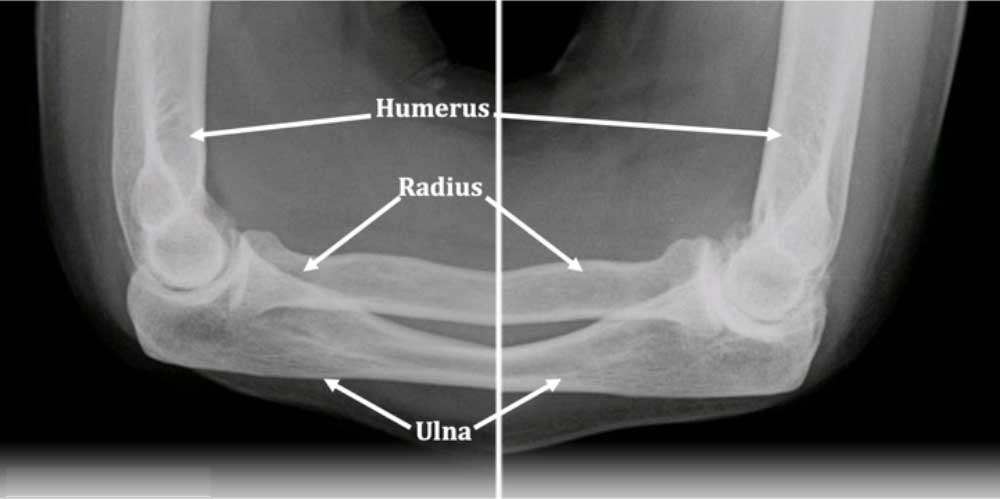

Διάγνωση

Η διάγνωση βασίζεται σε:

• Κλινική εξέταση από ορθοπεδικό.

• Ακτινογραφίες: δείχνουν φθορά χόνδρου, οστεόφυτα, στένωση αρθρικού διαστήματος.

• Μαγνητική τομογραφία: για λεπτομερή εικόνα χόνδρου, οστών και μαλακών μορίων.